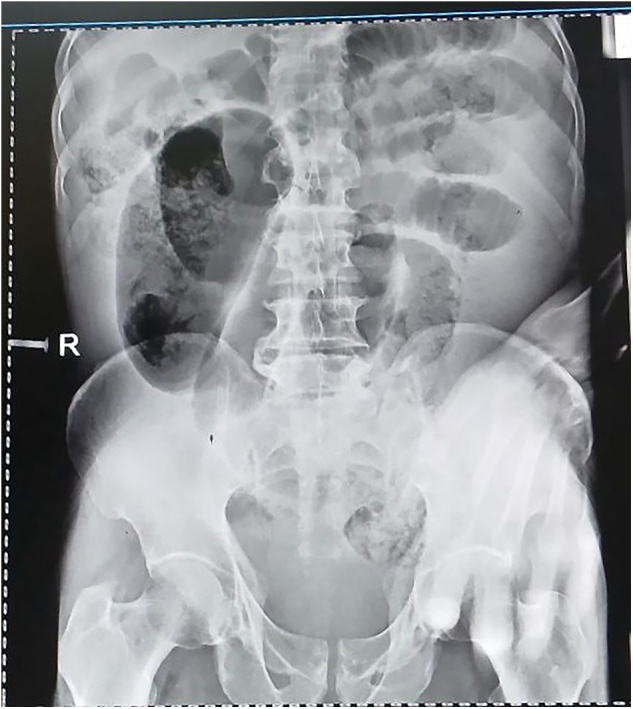

Presentation of case: A 60-year-old male from the Garbo region of Somali, Ethiopia, presented to the hospital after a a four-day history of intestinal obstruction symptoms. On examination, he was tachycardic and febrile, and exhibited diffuse abdominal tenderness. A diagnosis of intestinal obstruction with generalized peritonitis was made after abdominal x ray. The patient was resuscitated with fluids, started on antibiotics, and a nasogastric tube was placed. Emergency laparotomy revealed ileosigmoid knotting with gangrenous bowel. En bloc resection of the affected ileum and sigmoid colon was performed. An ileo-jejunal anastomosis and an end colostomy were constructed. Despite these interventions, the patient succumbed to uncontrolled sepsis on the fourth postoperative day.